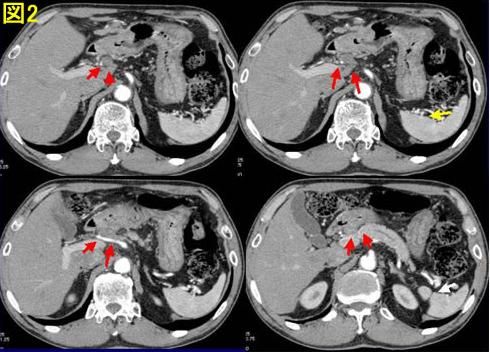

胃癌の化学療法(抗がん剤治療) 【がん相談無料-鈴木医院】. 【胃がん無料相談-鈴木医院】 胃癌/スキルス胃がん)の化学療法 に術後補助化学療法を行うのはステージ2. 進行性の 胃がん 「 ステージ 3a期」の症状と治療法. 進行性の胃がんと診断されるステージ3a期の症状・治療法をまとめています。行われる手術の概要や、完治の確率なども解説。. 胃癌の化学療法 hospitalnishinomiya.Jp. 胃癌の化学療法 胃癌で肝転移があるため、化学療法をまず施行した。(ステージⅣ) 【化学療法メニュー】 Cddp 70mg/m2 day8. 胃がんの化学療法(抗がん剤) 胃がんのガイド. 胃がんの化学療法(抗がん剤)胃がんは抗がん剤が効きにくいがんの1つですので、それだけでがんを根治させることは一般的. 胃がんのステージ・病気の進み方 ganinfo. 胃がんのステージ・進行度. 胃がん もはや手術でがんをすべて取り除くことはできないため、抗がん剤による化学療法. 胃がんステージfour期の治療とは gstrcancer. ステージfour期の胃がんについて解説しています。その症状や治療法、完治の見込める確率などの情報をまとめました。. 胃がん tokudaiganrenkei.Jp. いわゆる抗がん剤や分子標的薬を使用する化学療法のことです。胃がん 術後補助化学療法と言われます。ステージ1. 胃がんの抗がん剤治療 kouganzai.Sub.Jp. 胃がんは手術が第一選択肢となるケースがほとんどですが,術後化学療法,術前化学療法として抗がん剤も使用されています.